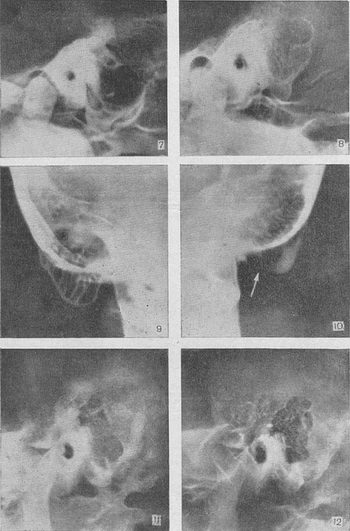

Для виявлення затемнених периантральных клітин і холестеатомной порожнини в області антрума слід користуватися проекцією Майєра. Порожнину субпериостального абсцесу, якщо вона не утворилася з кількох великих клітин (рис. 7), як правило, не має чітких обрисів, властивих холестеатоме. Верхівковий мастоїдит (абсцес Бецольда) можна не виявити, якщо обмежитися однією лише проекцією Шюллер. Рентгенограма по Стенверсу дозволяє виявити дефект внутрішньої кортикальної пластинки соскоподібного відростка (рис. 8-10).

Консервативне лікування хірургічних форм мастоидита при сприятливому перебігу веде до повної регенерації кісткової на місці абсцесу і до відновлення легкості збережених клітин, причому соскоподібний відросток з пневматичної стає Змішаним (рис. 11 і 12).

Рис. 7. Велика порожнина субпериостального абсцесу (гострий мастоїдит), що утворилася з кількох клітин (проекція Шюллер). Рис. 8-10. Лівобічний верхівковий мастоїдит (абсцес Бецольда): рис. 8 - клітини різко затемнені, верхівка соскоподібного відростка компактного будови: рис. 9 - видно клітини верхівки, зовнішня і внутрішня кіркові тонкі пластинки; рис. 10 - видно повний дефект внутрішньої кортикальної пластинки верхівки (стрілка), зовнішня кортикальна пластинка значної товщини. Рис. 11 і 12. Проекція Шюллер; гострий мастоїдит, консервативне лікування: рис. 11 - спонгиозно-пневматичний тип, початок захворювання, клітини скроневої кістки затемнені, на верхівці відростка видно деструктивний вогнище (симптом вторинного просвітлення): рис. 12 - стадія лікування, повне відновлення легкості клітин скроневої кістки, репаративні кісткові зміни на місці колишнього вогнища в сосцевидном відростку.